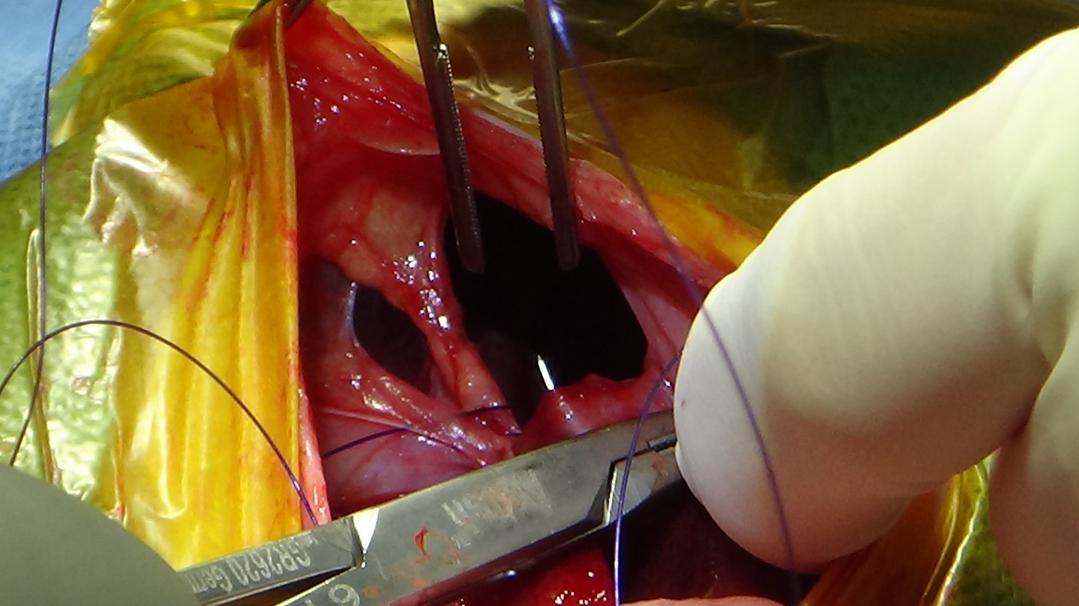

수술은 삼각형 모양의 횡격막 결손, 벌어져 융합되지 않은 caudal sternebrae를 확인할 수 있는 복부 정중 절개로 시행되었습니다.

탈장이 일어난 장기를 정상 위치로 되돌리고, 횡격막 결손은 등쪽에서부터 배쪽으로 단순 연속 봉합법을 통해 폐쇄했습니다.

봉합 후 흉강에 음압을 걸고, 복강을 세척하면서 다시 한번 횡격막의 완전성을 확인했습니다.